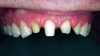

Fig 18. Preoperative radiographs of periodontally compromised mandibular anterior teeth that are treatment-planned for a direct placement fiber-reinforced resin splint.

Figure 18

Fig 19. Preoperative lingual view before scaling and root planing.

Figure 19